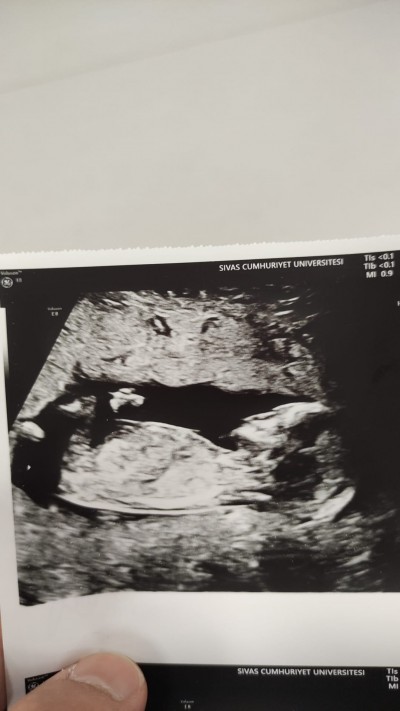

Cinsiyet tahmini anlayan varmı gebelik haftası 13+3 :)

image